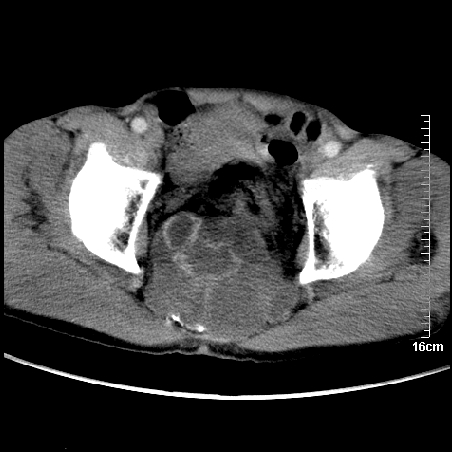

标题: CT16886:骶尾部占位:1.脊索瘤?2.巨细胞瘤? [打印本页]

标题: CT16886:骶尾部占位:1.脊索瘤?2.巨细胞瘤?

增强:

1、骶尾部巨大软组织肿块,部分骶尾骨以被软组织肿块代替,呈不规则侵蚀;病变突向盆腔内;增强扫描病变呈不均质强化;首先考虑脊索瘤。不支持的一点就是病变内无钙化。

2、发生于骶尾椎者须与骨巨细胞瘤鉴别,骨巨细胞瘤一般发在上疗骶椎,肿瘤内无钙化,一般无侵袭性生长的表现。